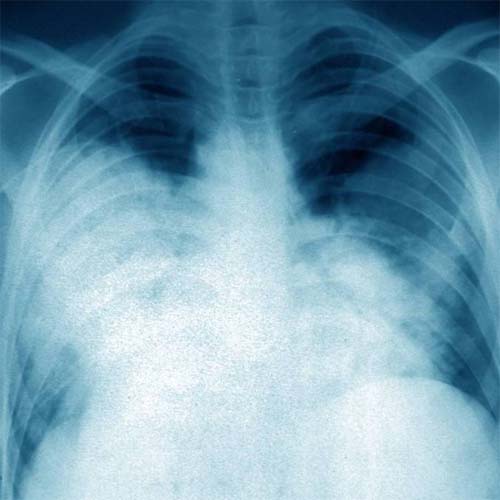

A Legionella pneumophila é uma bactéria do tipo bacilo Gram-negativo, que, segundo o Manual MSD de Diagnóstico e Tratamento, “frequentemente causa pneumonia com aspectos extrapulmonares”.

O guia médico descreve a infecção por legionela como uma síndrome semelhante à gripe, em que os pacientes apresentam febre, calafrios, mal-estar, dor no corpo e confusão.

Também podem surgir náuseas, diarreia e dor abdominal. Quando a doença evolui para a pneumonia, é comum haver falta de ar, dor no peito e hemoptise (expectoração de sangue).